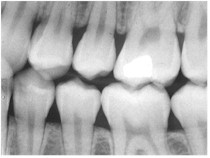

A dental x-ray requires holding a piece

of film behind the teeth